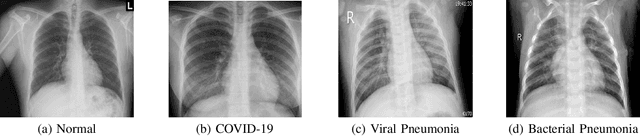

Abstract:This paper addresses the new problem of automated screening of coronavirus disease 2019 (COVID-19) based on chest X-rays, which is urgently demanded toward fast stopping the pandemic. However, robust and accurate screening of COVID-19 from chest X-rays is still a globally recognized challenge because of two bottlenecks: 1) imaging features of COVID-19 share some similarities with other pneumonia on chest X-rays, and 2) the misdiagnosis rate of COVID-19 is very high, and the misdiagnosis cost is expensive. While a few pioneering works have made much progress, they underestimate both crucial bottlenecks. In this paper, we report our solution, discriminative cost-sensitive learning (DCSL), which should be the choice if the clinical needs the assisted screening of COVID-19 from chest X-rays. DCSL combines both advantages from fine-grained classification and cost-sensitive learning. Firstly, DCSL develops a conditional center loss that learns deep discriminative representation. Secondly, DCSL establishes score-level cost-sensitive learning that can adaptively enlarge the cost of misclassifying COVID-19 examples into other classes. DCSL is so flexible that it can apply in any deep neural network. We collected a large-scale multi-class dataset comprised of 2,239 chest X-ray examples: 239 examples from confirmed COVID-19 cases, 1,000 examples with confirmed bacterial or viral pneumonia cases, and 1,000 examples of healthy people. Extensive experiments on the three-class classification show that our algorithm remarkably outperforms state-of-the-art algorithms. It achieves an accuracy of 97.01%, a precision of 97%, a sensitivity of 97.09%, and an F1-score of 96.98%. These results endow our algorithm as an efficient tool for the fast large-scale screening of COVID-19.